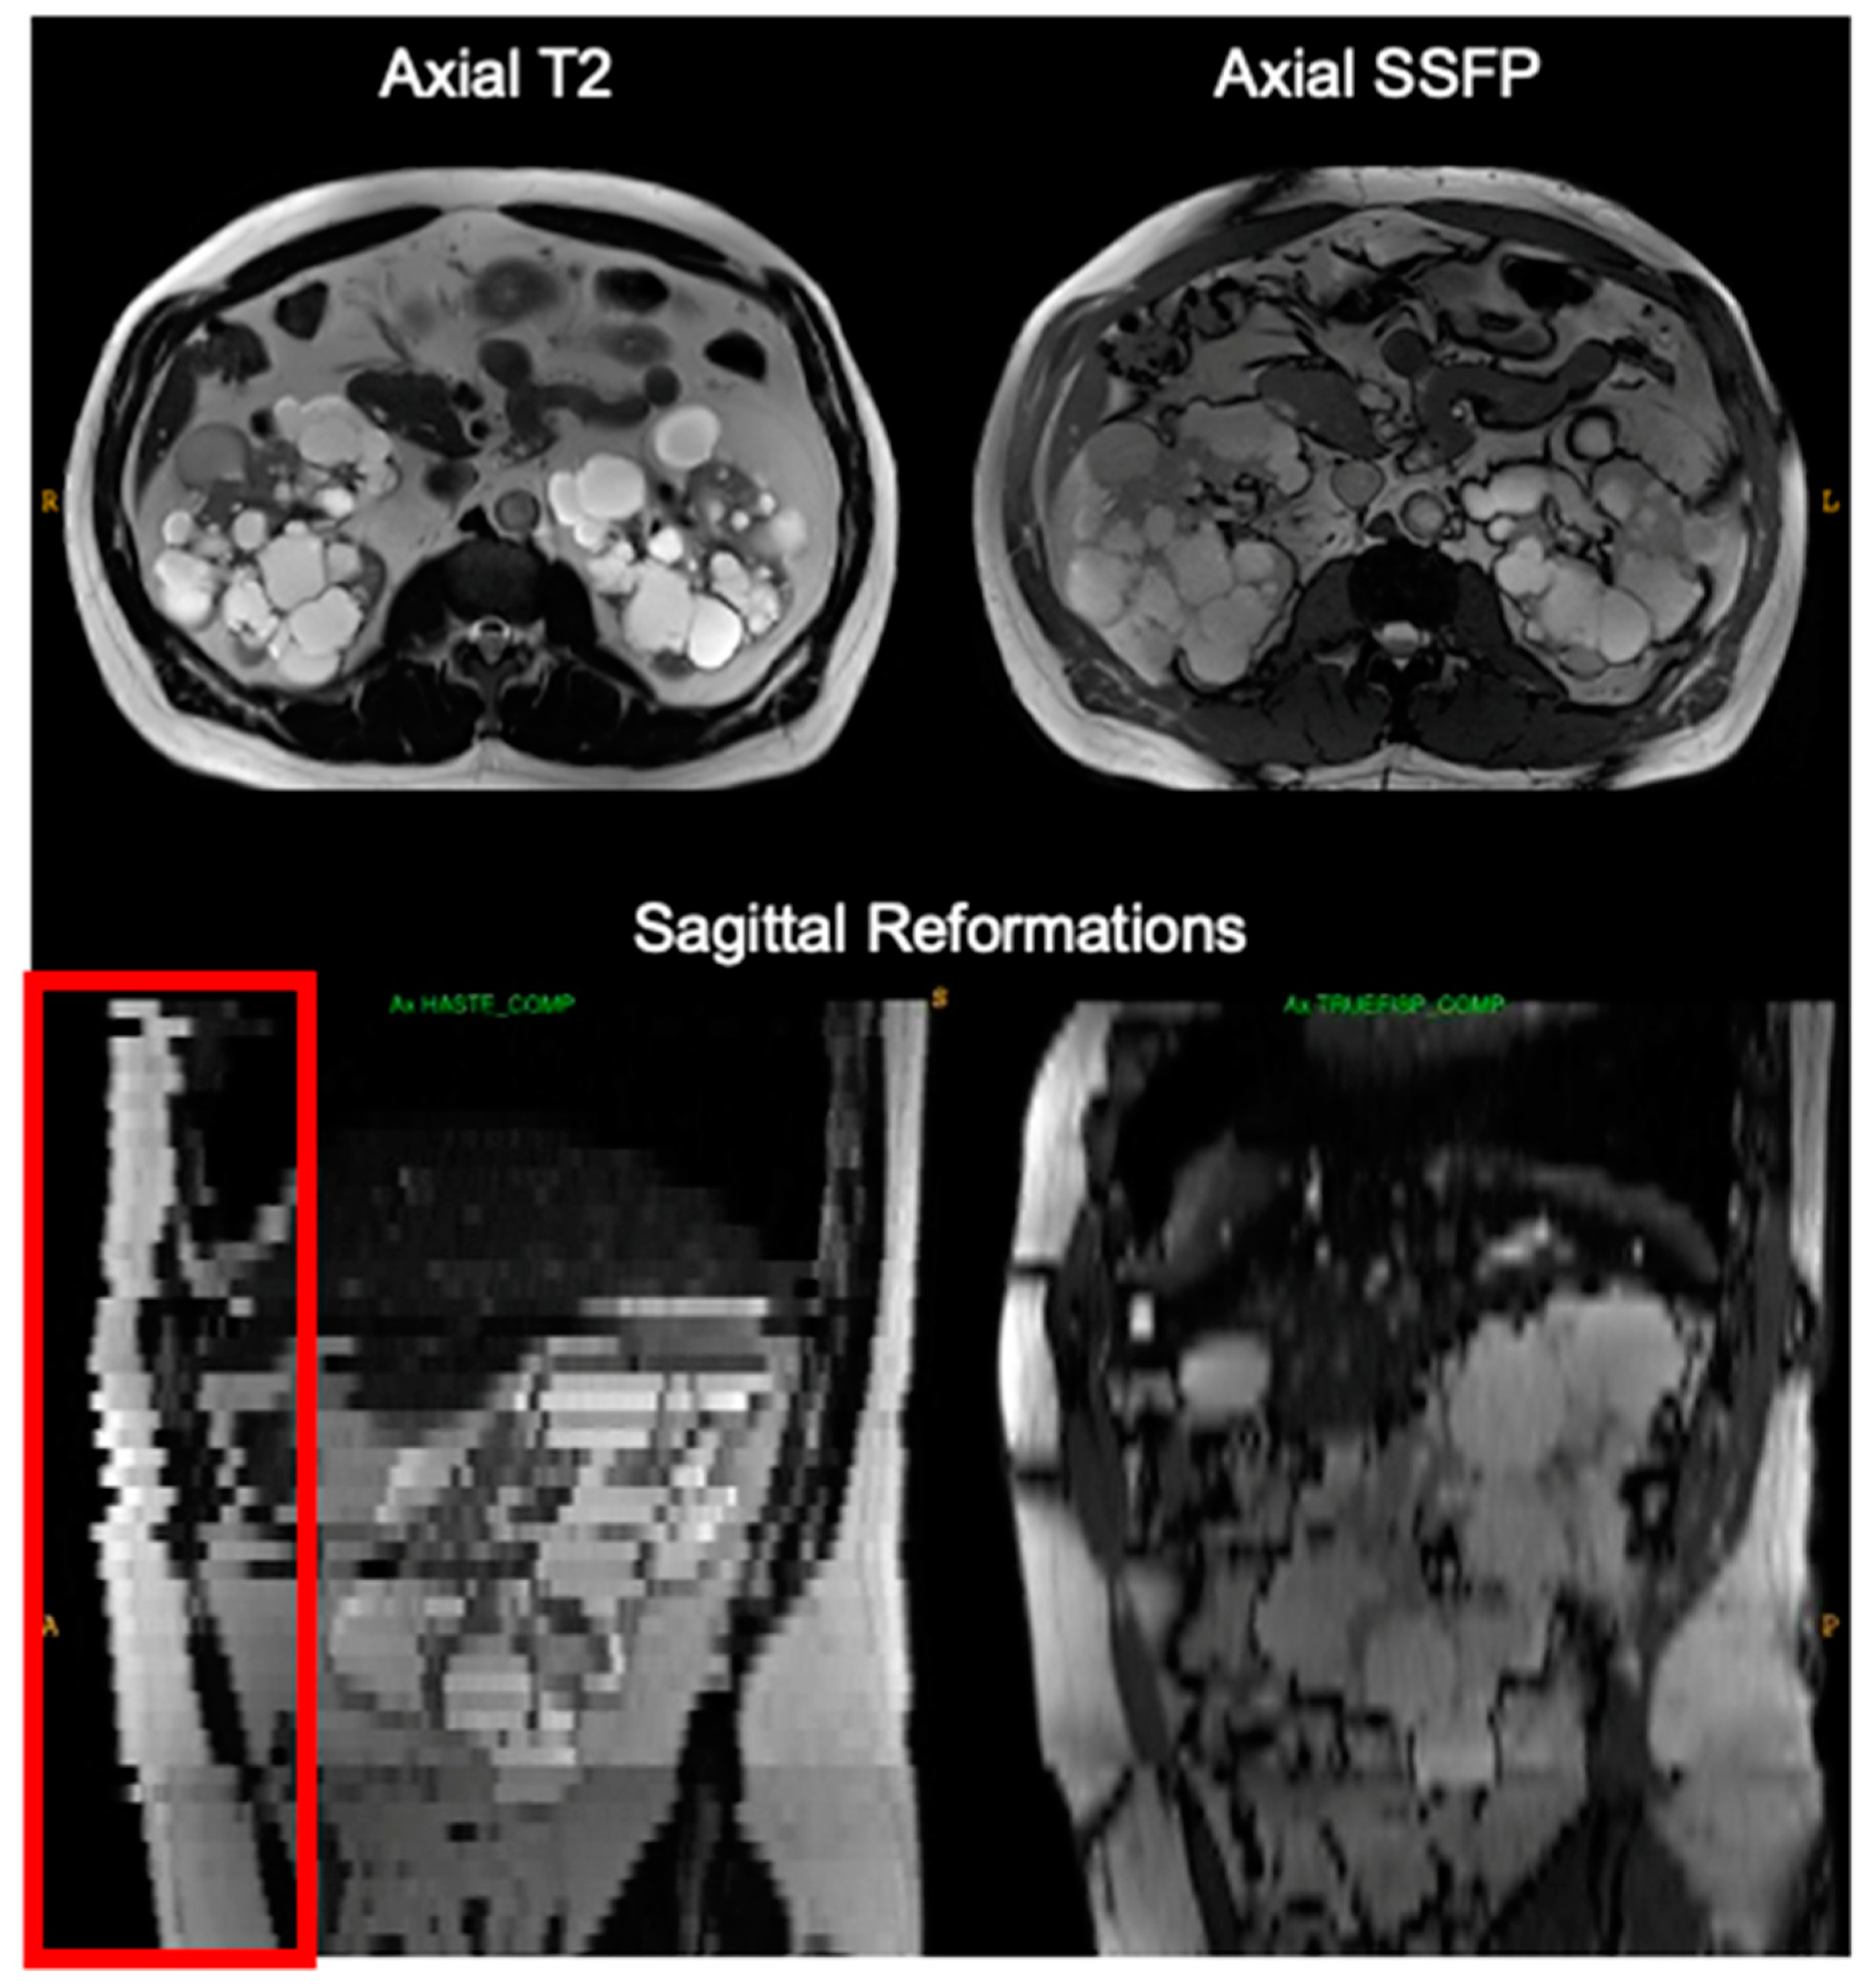

Breathing during scanning caused slice misregistration evident on orthogonal reconstructions, e.g., on coronal reformations of axial acquisitions and vice versa (Figure 3). Duplicated or missing kidney slices but not necessarily bilaterally were identified affecting 35 pulse sequences (6% of total pulse sequences) and impacting 25% of exams. This higher-than-normal incidence of breathing motion errors during abdominal MRI acquisition is expected in ADPKD patients, given the limited lung expansion room due to increased kidney volume pushing up on the diaphragm and the extended scanning time needed to cover the enlarged liver/kidneys. These errors resulted in a median 7.8% difference from the reference TKV, ranging from −14% to 23%, and primarily affected T2 images (in 31 out of 35 cases). Specifically, breathing motion in axial T2 scans resulted in a TKV deviation from the reference TKV with a median of 9.3% and an interquartile range of 2.6% to 13%. For comparison, breathing motion in coronal T2 scans led to similar TKV deviation with a median of 7.8% and an interquartile range of 1.6% to 11%.

Figure 3. Breathing motion during scanning axial T2 (left) is not apparent on axial images in the plane of acquisition (top left) but is easily detected on sagittal (lower left) reformations with boundary discontinuities (red box). There was no breathing motion on the next pulse sequence, axial SSFP (right). This slice misregistration cannot be easily corrected but TKV measurement reproducibility is improved by excluding it from the TKV calculation.